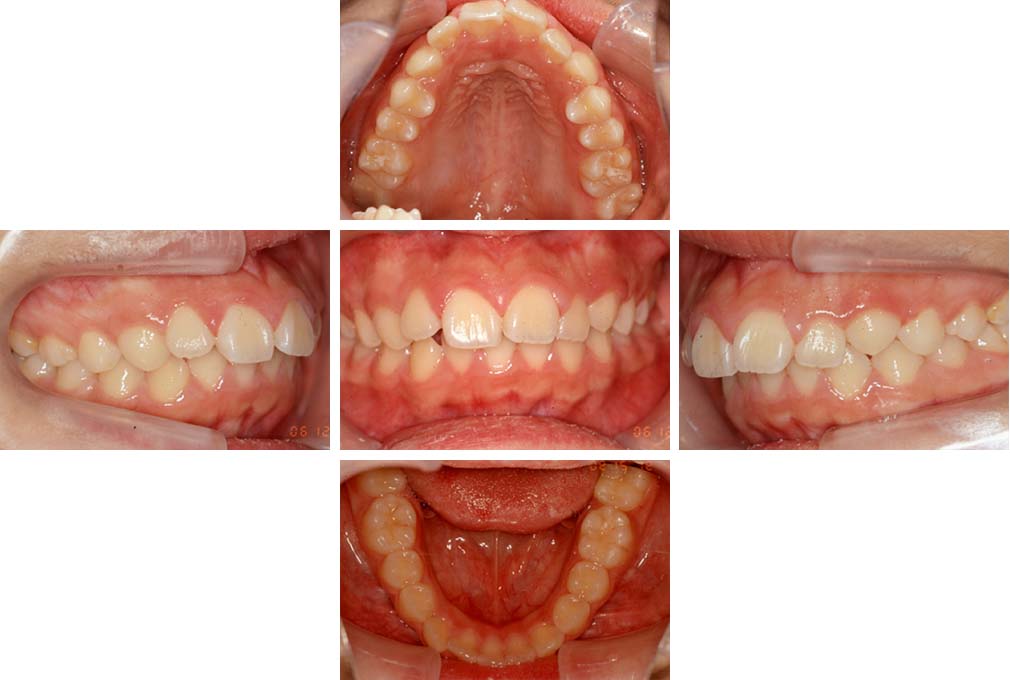

CASE:01

叢生を伴う骨格性上顎前突

初診時年齢 15歳10カ月

性別 男性

上顎前歯の前突と叢生を主訴として来院された。大臼歯関係は左右側ともにⅡ級で上顎の方が前方に位置していた。叢生を伴う骨格性上顎前突と診断し、上下顎小臼歯抜歯を行っていただきマルチブラケット装置に顎外固定装置を併用して動的治療を行った。顎外固定装置や矯正用ゴムの使用など協力状態も良好で、動的治療期間2年0カ月、調整来院20回でマルチブラケット装置を撤去し保定へ移行した。動的治療終了後10年0カ月を経過したが保定移行時とほぼ同様の咬合状態で良好な状態を保っていた。

治療前

15歳10か月

治療後

動的治療期間2年0カ月

18歳5か月

10年経過

動的治療終了後10年0カ月

28歳5か月